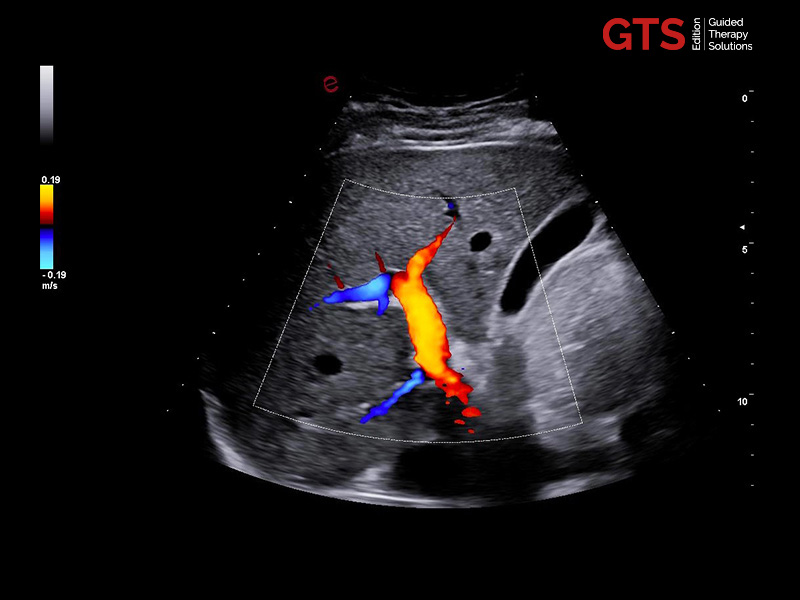

microV shows vascularization and improves the visualization of slow blood flow in tiny vessels.

An adaptive algorithm identifies the blood flow signals and separates them from background tissue and motion artefacts. By eliminating background noise, microV technology enables an advanced hemodynamic evaluation with maximum sensitivity and spatial resolution.

microV to study the micro-vascularization of the suspicious area